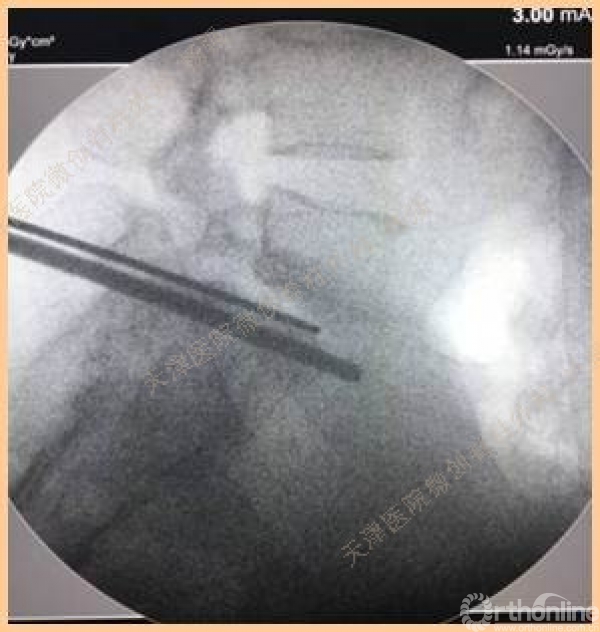

可动式间盘镜辅助下TLIF手术治疗 腰椎峡部裂性滑脱

以下是活动中荣获二等奖的天津医院微创脊柱外科杨强医生的获奖病例。